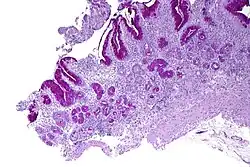

Micrograph showing nodular enterochromaffin-like cell hyperplasia, as demonstrated with chromogranin A immunostaining, in the body of the stomach. Parietal cells are not readily apparent. These changes are in keeping with autoimmune metaplastic atrophic gastritis, a histologic correlate of vitamin B12 deficiency anemia. | |